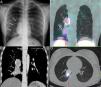

Clinical ReportsCase 1 (Fig. 1)A 16-year-old girl with a 3-year history of recurrent pneumonia, who was hospitalized due to a new episode of persistent cough. Diminished breath sounds in the right lung base and leukocytosis with left shift were identified and opacity with signs of atelectasis of the right lower lobe (RLL) were seen on standard chest X-ray (Fig. 1).

(A) Standard posteroanterior chest X-ray: right basal opacity with signs of atelectasis in right lower lobe (RLL) (arrows). (B) Coronal contrast-enhanced computed tomography (CT): right hilar mass (dotted arrow), enhanced after contrast administration, causing RLL atelectasis (solid arrow). (C) Chest SPECT-CT. Coronal slice: radiotracer hotspot in right hilar region, suggestive of neuroendocrine tumor (dotted arrow). Another less intense radiotracer uptake focus, below the hotspot, located in an area of pneumonitis with atelectasis (solid arrows). (D) Chest SPECT-CT. Axial slice: radiotracer hotspot located in right hilar mass (dotted arrow).

Contrast-enhanced computed tomography (CT) revealed a right parahilar mass (3.5cm) with lumpy calcifications, enhanced with contrast, compressing the intermediate bronchus and causing obstructive atelectasis of the RLL with mucoid impactions. A lymphadenopathy (1cm) was observed in right parahilar region.

Scintigraphy was requested to confirm suspected bronchial carcinoid tumor and to complete the evaluation. A whole body scan (WBS) and chest SPECT-CT were performed, revealing a focus of increased uptake or “hotspot” in the right parahilar mass, indicative of NET. Diffuse, mildly intense uptake was also observed on the SPECT-CT below the hotspot, due to pneumonitis.